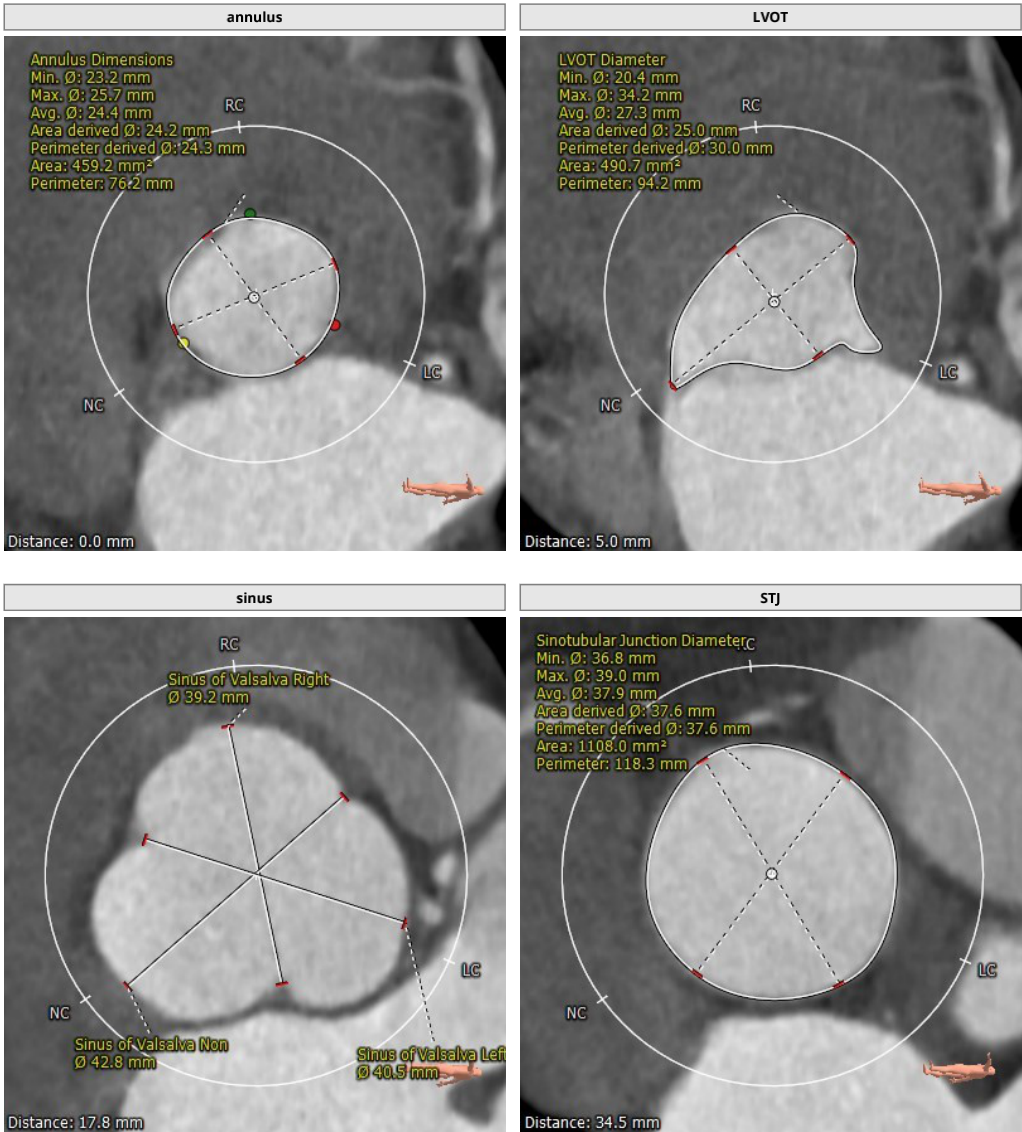

主动脉根部CT解剖影像

影像分析提示为三叶瓣结构,瓣叶无增厚及钙化,根据瓣环平面周长所得直径:24.3mm,左室流出道明显大于瓣环平面呈喇叭形,STJ无明显内收与升主动脉呈直筒形,左右冠开口高度可,窦部空间大,心脏角度72度横位心。